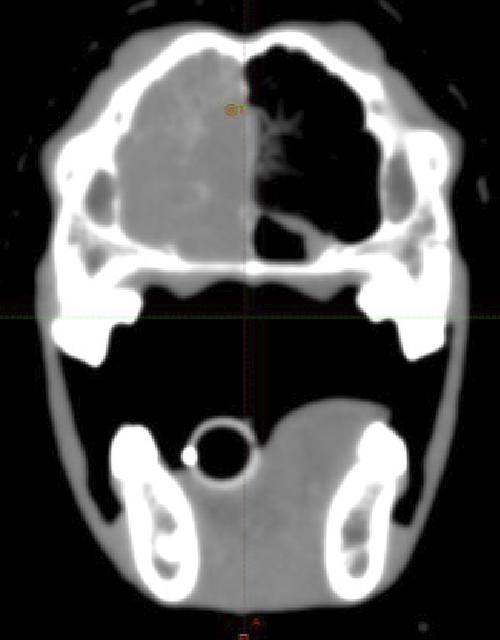

鼻腔内腺癌における放射線治療4ヶ月後の

顕著な鼻腔内病変消失の一例

放射線治療前

放射線治療後